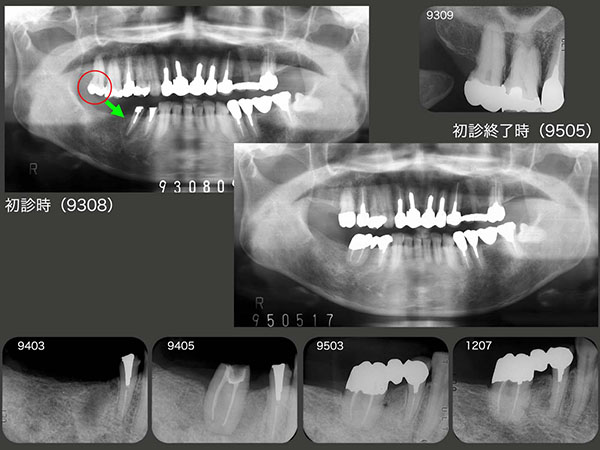

3.片側遊離端欠損をブリッジで対応

1993年9月初診,52歳の女性.右下の補綴を希望.94年4月,右上7をドナ−歯とし,右下6部に移植した.また,付着歯肉の不足を補うため,7月に口蓋より採取した歯肉のフリーグラフトを行った.95年3月,右下⑥5④のブリッジを装着した.2013年8月,初診終了後18年,経過は順調であったが残念なことに,同年他界された.